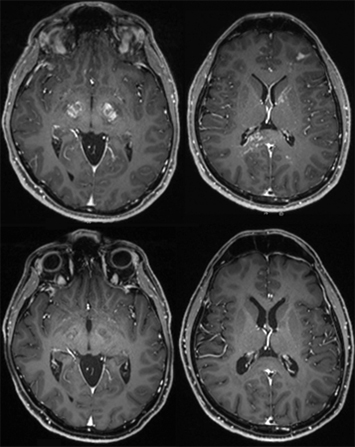

A male patient in his 40s presented to outside hospital after developing left facial droop, slurred speech and urinary incontinence while traveling. The medical history was remarkable for Tdap vaccination administered three days prior to the commencement of his symptoms. MRI of the brain and spinal cord showed multifocal enhancing confluent white matter lesions. He was diagnosed with acute disseminated encephalomyelitis (ADEM). He was subsequently started on high-dose steroids (solumedrol 1 gram) daily x five days followed by a steroid taper. After returning home he presented to Cedars-Sinai ED one month later with similar symptoms of worsening slurred speech and altered gait. He was again started on steroids with improvement of his symptoms and was discharged home but was admitted again two weeks later with worsening symptoms. MRI imaging showed multifocal supratentorial and infratentorial parenchymal T2/FLAIR signal abnormality involving the cerebral hemispheres, deep gray/white matter, corpus callosum (splenium) and brainstem white matter tracts, raising suspicion for neoplastic process [left image, upper panel]. He was placed on IVIG (2 grams/kg) over five days and was continued on prednisone 60 milligrams daily. Serum autoimmune encephalopathy panel, NMO and MOG cell-based assays were all negative. Ultimately, he underwent a brain biopsy which showed involvement by diffuse large B-cell lymphoma [right image]. It was BCL6 rearranged by FISH while NGS identified mutations in CDKN2A, PIM1, CD79B, CTCF, ATM and SOCS1.

He was treated with three cycles of methotrexate (dose 7.6 grams/m2), two cycles of temozolomide (80 milligrams for five days on and 23 days off), and rituximab and achieved clinical remission. MRI showed complete resolution of mass lesions [left image, lower panel]. He subsequently underwent conditioning chemotherapy with carmustine (400 milligrams/m2)/ thiotepa (5 milligrams/kg q12 hours x two days) followed by and autologous stem cell transplant (total of 3.97x106/kilograms CD34+ cells infused).